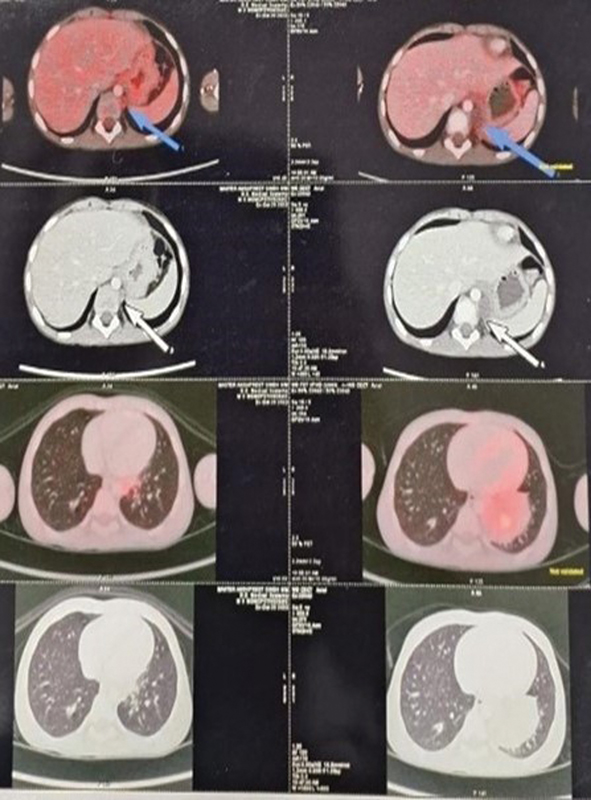

The positron emission tomography (PET) scan for staging revealed the presence of an irregularly shaped, metabolically active soft tissue mass in the lower left lung lobe. This finding suggests the possibility of primary neoplastic disease ([Fig. 2]). The mediastinal and left retrocrural regions showed small, inactive lymph nodes, indicating the presence of nearby metastatic lymph nodes. No other abnormal metabolically active lesions were found in the body. A biopsy of the lung mass found a malignant small round cell tumor, suggesting a possible diagnosis of neuroendocrine small-cell carcinoma. Microscopically, the tumor cells were arranged in sheets and occasionally displayed rosette formation. These small, round-to-oval cells exhibited a blue appearance, minimal cytoplasm, inconspicuous nucleoli, and slight overlap with nuclear molding. The stroma was thin and delicate, with occasional mitosis and patchy calcification. Immunohistochemistry (IHC) of the biopsy revealed thyroid transcription factor-1 (TTF-1) and synaptophysin positivity, while CK7 and chromogranin showed focal positivity. The biomarkers CD56, desmin, CD99, vimentin, and NKX 2.2 were found to be negative ([Fig. 3]). Fluorescence in situ hybridization (FISH) analysis revealed no evidence of EWSR1 gene rearrangement in 100% of the cells studied. Next-generation sequencing did not reveal any clinically relevant pathogenic mutations or fusions.

The nature of the disease and the patient's prognosis were explained in detail to the patient's parents, who provided their consent to start chemotherapy. The patient began a chemotherapy regimen consisting of etoposide (100 mg/m2/dose) and carboplatin (350 mg/m2/dose) from days 1 to 3, following the latest CHEST recommendations for initial treatment.[9] Chemotherapy led to significant side effects, including intense nausea, vomiting, and neutropenia. He was given oral ondansetron and injectable filgrastim to manage the side effects. During his last follow-up on August 1, 2024, the high-resolution computed tomography of the chest revealed a small atelectatic area adjacent to the pericardium, likely reflecting posttreatment changes ([Fig. 4]). The patient is currently in remission and continues to be monitored closely.

| Figure 4: (A, B) Posttreatment follow-up chest high-resolution computed tomography images demonstrating a small area of atelectasis in the left lower lobe.

| Figure 3: Immunohistochemistry showing synaptophysin marker positivity.